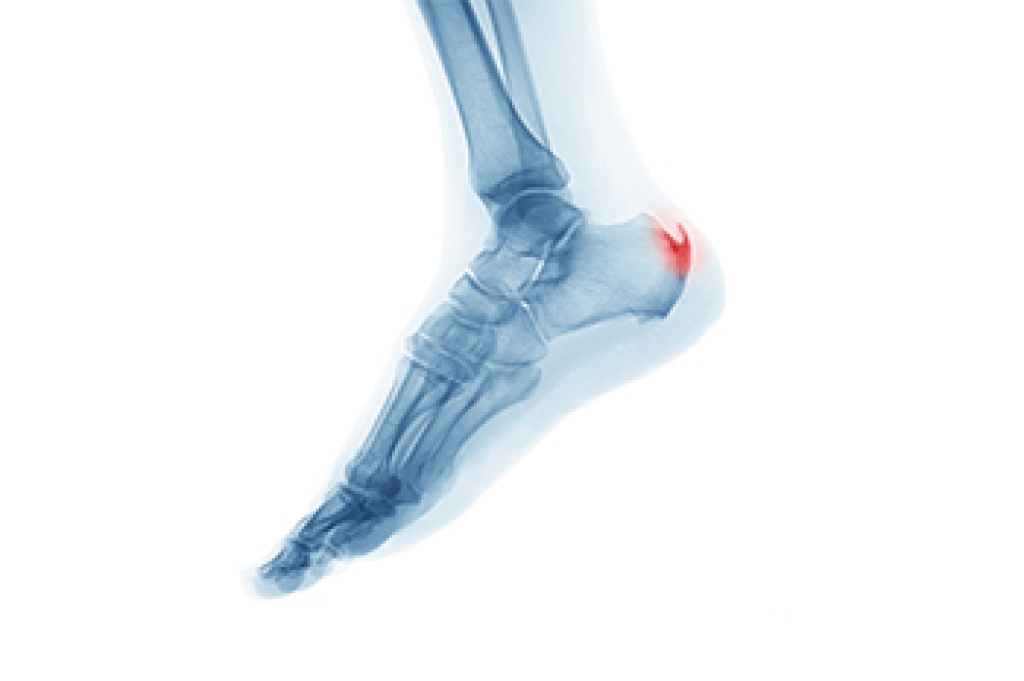

Ankle injuries in basketball often occur due to the dynamic movements and high-impact nature of the sport. One common injury is the ankle sprain, which happens when the ligaments supporting the ankle stretch or tear, usually as a result of sudden twists, turns, or awkward landings. These sprains can range from mild to severe, causing pain, swelling, and limited mobility. Another significant concern is ankle fractures, which occur when one or more of the bones surrounding the ankle joint break, often due to forceful impacts or collisions. Both sprains and fractures require timely attention to prevent further damage and promote proper healing. Proper warm-up routines, wearing supportive footwear, and practicing correct landing techniques can help reduce the risk of ankle injuries in basketball players. Additionally, implementing strength and balance exercises to improve ankle stability and flexibility can aid in injury prevention. If you have sustained an ankle injury from playing basketball, it is suggested that you schedule an appointment with a podiatrist for treatment.

Foot and ankle injuries are a common occurrence when it comes to athletes of any sport. While many athletes dismiss the initial aches and pains, the truth is that ignoring potential foot and ankle injuries can lead to serious problems. As athletes continue to place pressure and strain the area further, a mild injury can turn into something as serious as a rupture and may lead to a permanent disability. There are many factors that contribute to sports related foot and ankle injuries, which include failure to warm up properly, not providing support or wearing bad footwear. Common injuries and conditions athletes face, including:

Sports related injuries are commonly treated using the RICE method. This includes rest, applying ice to the injured area, compression and elevating the ankle. More serious sprains and injuries may require surgery, which could include arthroscopic and reconstructive surgery. Rehabilitation and therapy may also be required in order to get any recovering athlete to become fully functional again. Any unusual aches and pains an athlete sustains must be evaluated by a licensed, reputable medical professional.